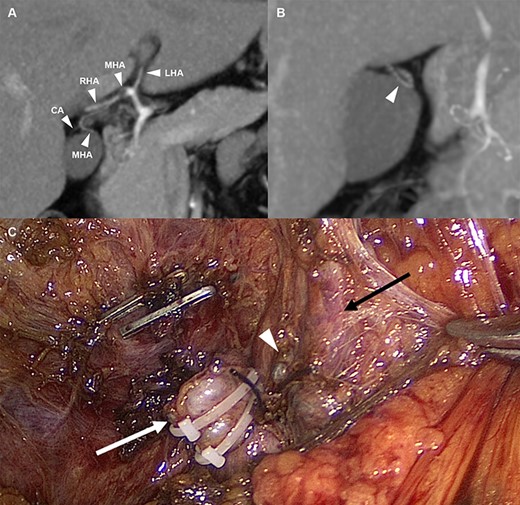

A 42-year-old man visited the outpatient department complaining of chronic epigastric pain for the past 1 year, without surgical or medical history. The frequency and severity of epigastric pain had increased since 6 months. Ultrasonography revealed gallbladder wall thickening with stones, indicating chronic cholecystitis, and it was decided to perform laparoscopic cholecystectomy. During the preoperative evaluation, an interesting finding was observed on computed tomography. The patient had a cystic artery arising from the MHA (Fig. 1A). An MHA derived from the hilum of the proper hepatic artery runs along the medial border of the gallbladder and enters segment IV (Fig. 1B).

(A) Arterial anatomy; the MHA derived from the hilum of the hepatic artery and the CA arising from the MHA (B) The MHA that runs into segment IV (C) Anatomical structures after cholecystectomy; white arrow: cystic duct stump, white wedge: CA stump, and black arrow: MHA. LHA, left hepatic artery; MHA, middle hepatic artery; RHA, right hepatic artery; CA, cystic artery.